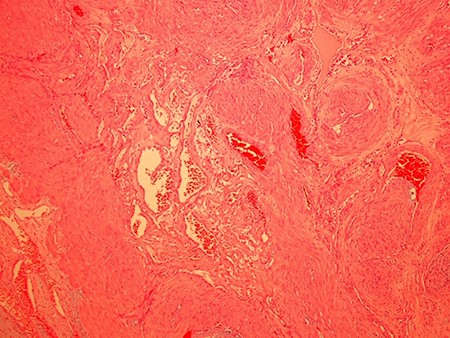

Because of its hypervascularity, the neck tumour was deemed not amenable to ultrasound-guided biopsy. Hence, the patient subsequently underwent an excisional biopsy, where the operative findings were that of a vascular-rich mass superior to the medial end of the clavicle and wedged between the two heads of SCM. Histopathological analysis determined that the mass was composed of thick-walled blood vessels with prominent muscle (Fig. 3). There was focal myxoid degenerative change and focal chondroid metaplasia with no evidence of malignancy, suggestive of an angioleiomyoma. The patient was reviewed 3 months post-operatively and was recovering well.

A representative haematoxylin and eosin (H&E) histological image (100× magnification) of the right supraclavicular venous subtype angioleiomyoma showing variably sized blood vessels with thick walls and prominent muscle.